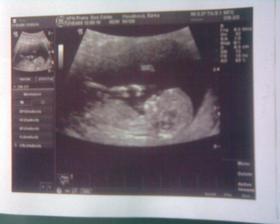

27.3 09 vyšetření screening dopdl dobře 🙂 miminko je zdravé má 11+5tt a 8cm žádná vývojová vada se nenašla. Jen placenta má rýhy jizvičky od hematomů,ale to prý nevadí to se zahojí.Hematomy už jsou pryč 🙂 28.5 Vyšetření a velký ultrazvuk ve 21tt dopadl dobře miminko zdravé vše bylo v pořádku , ukázal nám že to je kluk jako buk a váží už 413g .Také ve 21tt dává o sobě vědět už to není jen bublání v bříšku,ale semtam kopaneček a to tak dvakrát za den 🙂 4D ultrazvuk ve 25tt